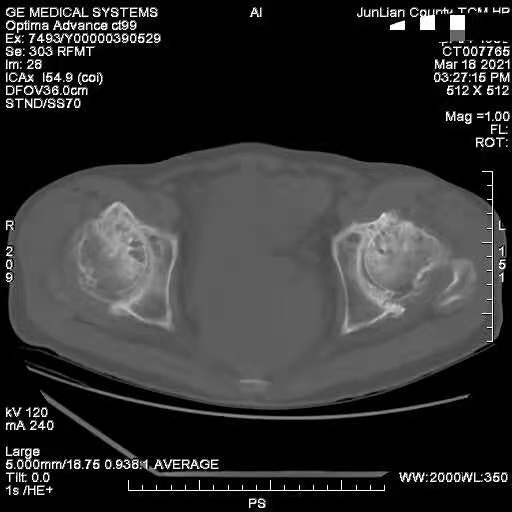

2.髋关节,双侧髋关节都是这样,我看一直考虑的股骨头缺血坏死,我觉得解释不通啊?这个病人是髋臼和股骨头广泛的囊变,但是关节面是完整的,没有看到塌陷,关节间隙变窄,有些地方看着关节骨性强直了,关节囊内软组织影增多、周围也有肿胀。我接触CT不久,看的比较少,劳烦老师帮忙看看。

3、两侧髋关节骨性关节炎改变,不考虑缺失坏死,MRI可进一步明确。

双髋关节改变,考虑类风湿性关节炎